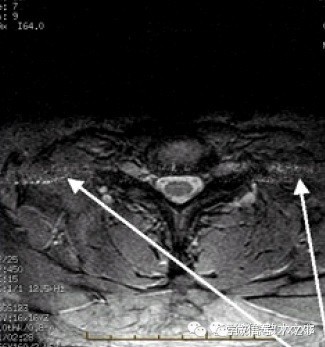

拉链伪影

自由感应衰减还没有完全衰减之前,180°脉冲的侧峰就与它产生重叠。或者领近层面不精确的射频脉冲造成一个未经相位编码就激励的回波。

伪影图像特点:

沿频率编码轴(0相位)交替的亮点与黑点组成的中心条带,或噪声带。